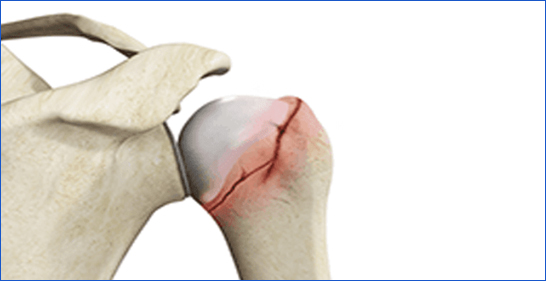

10. Shoulder Fracture

A break in the clavicle (collarbone), scapula (shoulder blade), or humerus (upper arm bone).

Icon Cause: Falls, sports injuries, or direct trauma.

Icon Symptoms: Shoulder pain, swelling, and limited arm movement.

Icon Treatment: Immobilization with a sling, surgery for severe fractures.